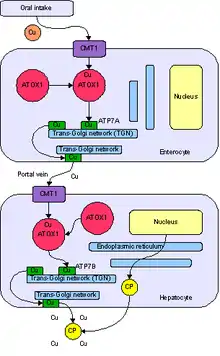

Copper enters the body through the digestive tract. A transporter protein on the cells of the small bowel, copper membrane transporter 1 (Ctr1; SLC31A1), carries copper inside the cells, where some is bound to metallothionein and part is carried by ATOX1 to an organelle known as the trans-Golgi network. Here, in response to rising concentrations of copper, an enzyme called ATP7A (Menkes' protein) releases copper into the portal vein to the liver. Liver cells also carry the CMT1 protein, and metallothionein and ATOX1 bind it inside the cell, but here, ATP7B links copper to ceruloplasmin and releases it into the bloodstream, as well as removing excess copper by secreting it into bile. Both functions of ATP7B are impaired in Wilson's disease. Copper accumulates in the liver tissue; ceruloplasmin is still secreted, but in a form that lacks copper (termed apo-ceruloplasmin) and is rapidly degraded in the bloodstream.[15]

When the amount of copper in the liver overwhelms the proteins that normally bind it, it causes oxidative damage through a process known as Fenton chemistry; this damage eventually leads to chronic active hepatitis, fibrosis (deposition of connective tissue), and cirrhosis. The liver also releases copper into the bloodstream that is not bound to ceruloplasmin. This free copper precipitates throughout the body, but particularly in the kidneys, eyes, and brain. In the brain, most copper is deposited in the basal ganglia, particularly in the putamen and globus pallidus (together called the lenticular nucleus); these areas normally participate in the coordination of movement and play a significant role in neurocognitive processes such as the processing of stimuli and mood regulation. Damage to these areas, again by Fenton chemistry, produces the neuropsychiatric symptoms seen in Wilson's disease.[15]